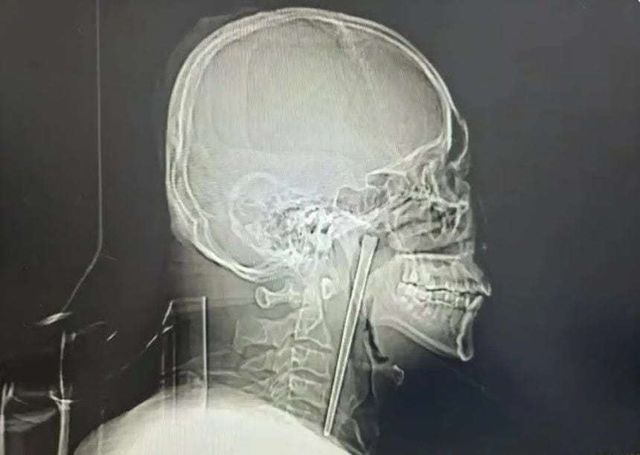

중국에서 한 남성이 길이 12㎝에 달하는 금속 젓가락이 목에 박힌 채로 8년간 생활하다가 뒤늦게 수술로 제거한 사실이 알려졌다.

19일(현지 시간) 사우스차이나모닝포스트(SCMP)에 따르면 중국 랴오닝성 다롄에 거주하는 왕 씨는 최근 다롄시 중심병원에서 목에 박혀 있던 젓가락을 제거하는 수술을 받았다.

보도에 따르면 왕 씨는 8년 전 음주 상태에서 식사를 하다 실수로 금속 젓가락을 삼켰다. 당시 왕 씨는 통증은 있었지만 호흡에는 문제가 없었고, 의료진이 목을 절개해 젓가락을 제거하는 수술을 권유했지만 이를 거부했다.

이후 왕 씨는 간헐적으로 이물감을 느꼈지만, 이를 음주로 인한 숙취 등 일시적인 증상이라 여기며 별다른 치료를 받지 않았다. 그러다 몇 주 전부터 아침마다 통증이 심해지고, 음식물을 삼킬 때 고통이 커지자 다시 병원을 찾았다.

진료를 맡은 의료진은 검사 결과 그의 연구개(입천장 뒤쪽 부위)에 금속 젓가락이 박혀 있는 것을 확인했다. 다행히 주변 점막이나 장기에는 큰 손상이 없었고, 성대 기능도 정상적으로 유지된 상태였다.

의료진은 환자가 목 절개를 거부했던 점을 고려해 입을 통한 최소 침습 수술을 진행했고, 길이 12㎝의 젓가락을 성공적으로 제거했다. 수술은 소량의 출혈만 발생한 채 비교적 순조롭게 마무리됐으며, 왕 씨는 회복 후 며칠 만에 퇴원한 것으로 전해졌다.송치훈 기자 sch53@donga.com